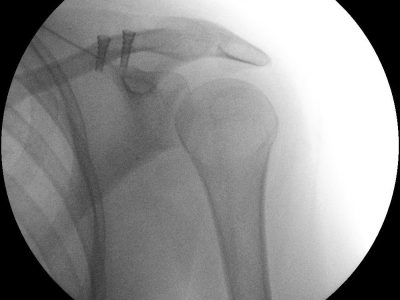

Παρακάτω παρατίθενται ακτινογραφίες καταγμάτων του άνω άκρου που αντιμετωπίζονται με εσωτερική οστεοσύνθεση ή επανορθωτική χειρουργική με αρθροπλαστική.